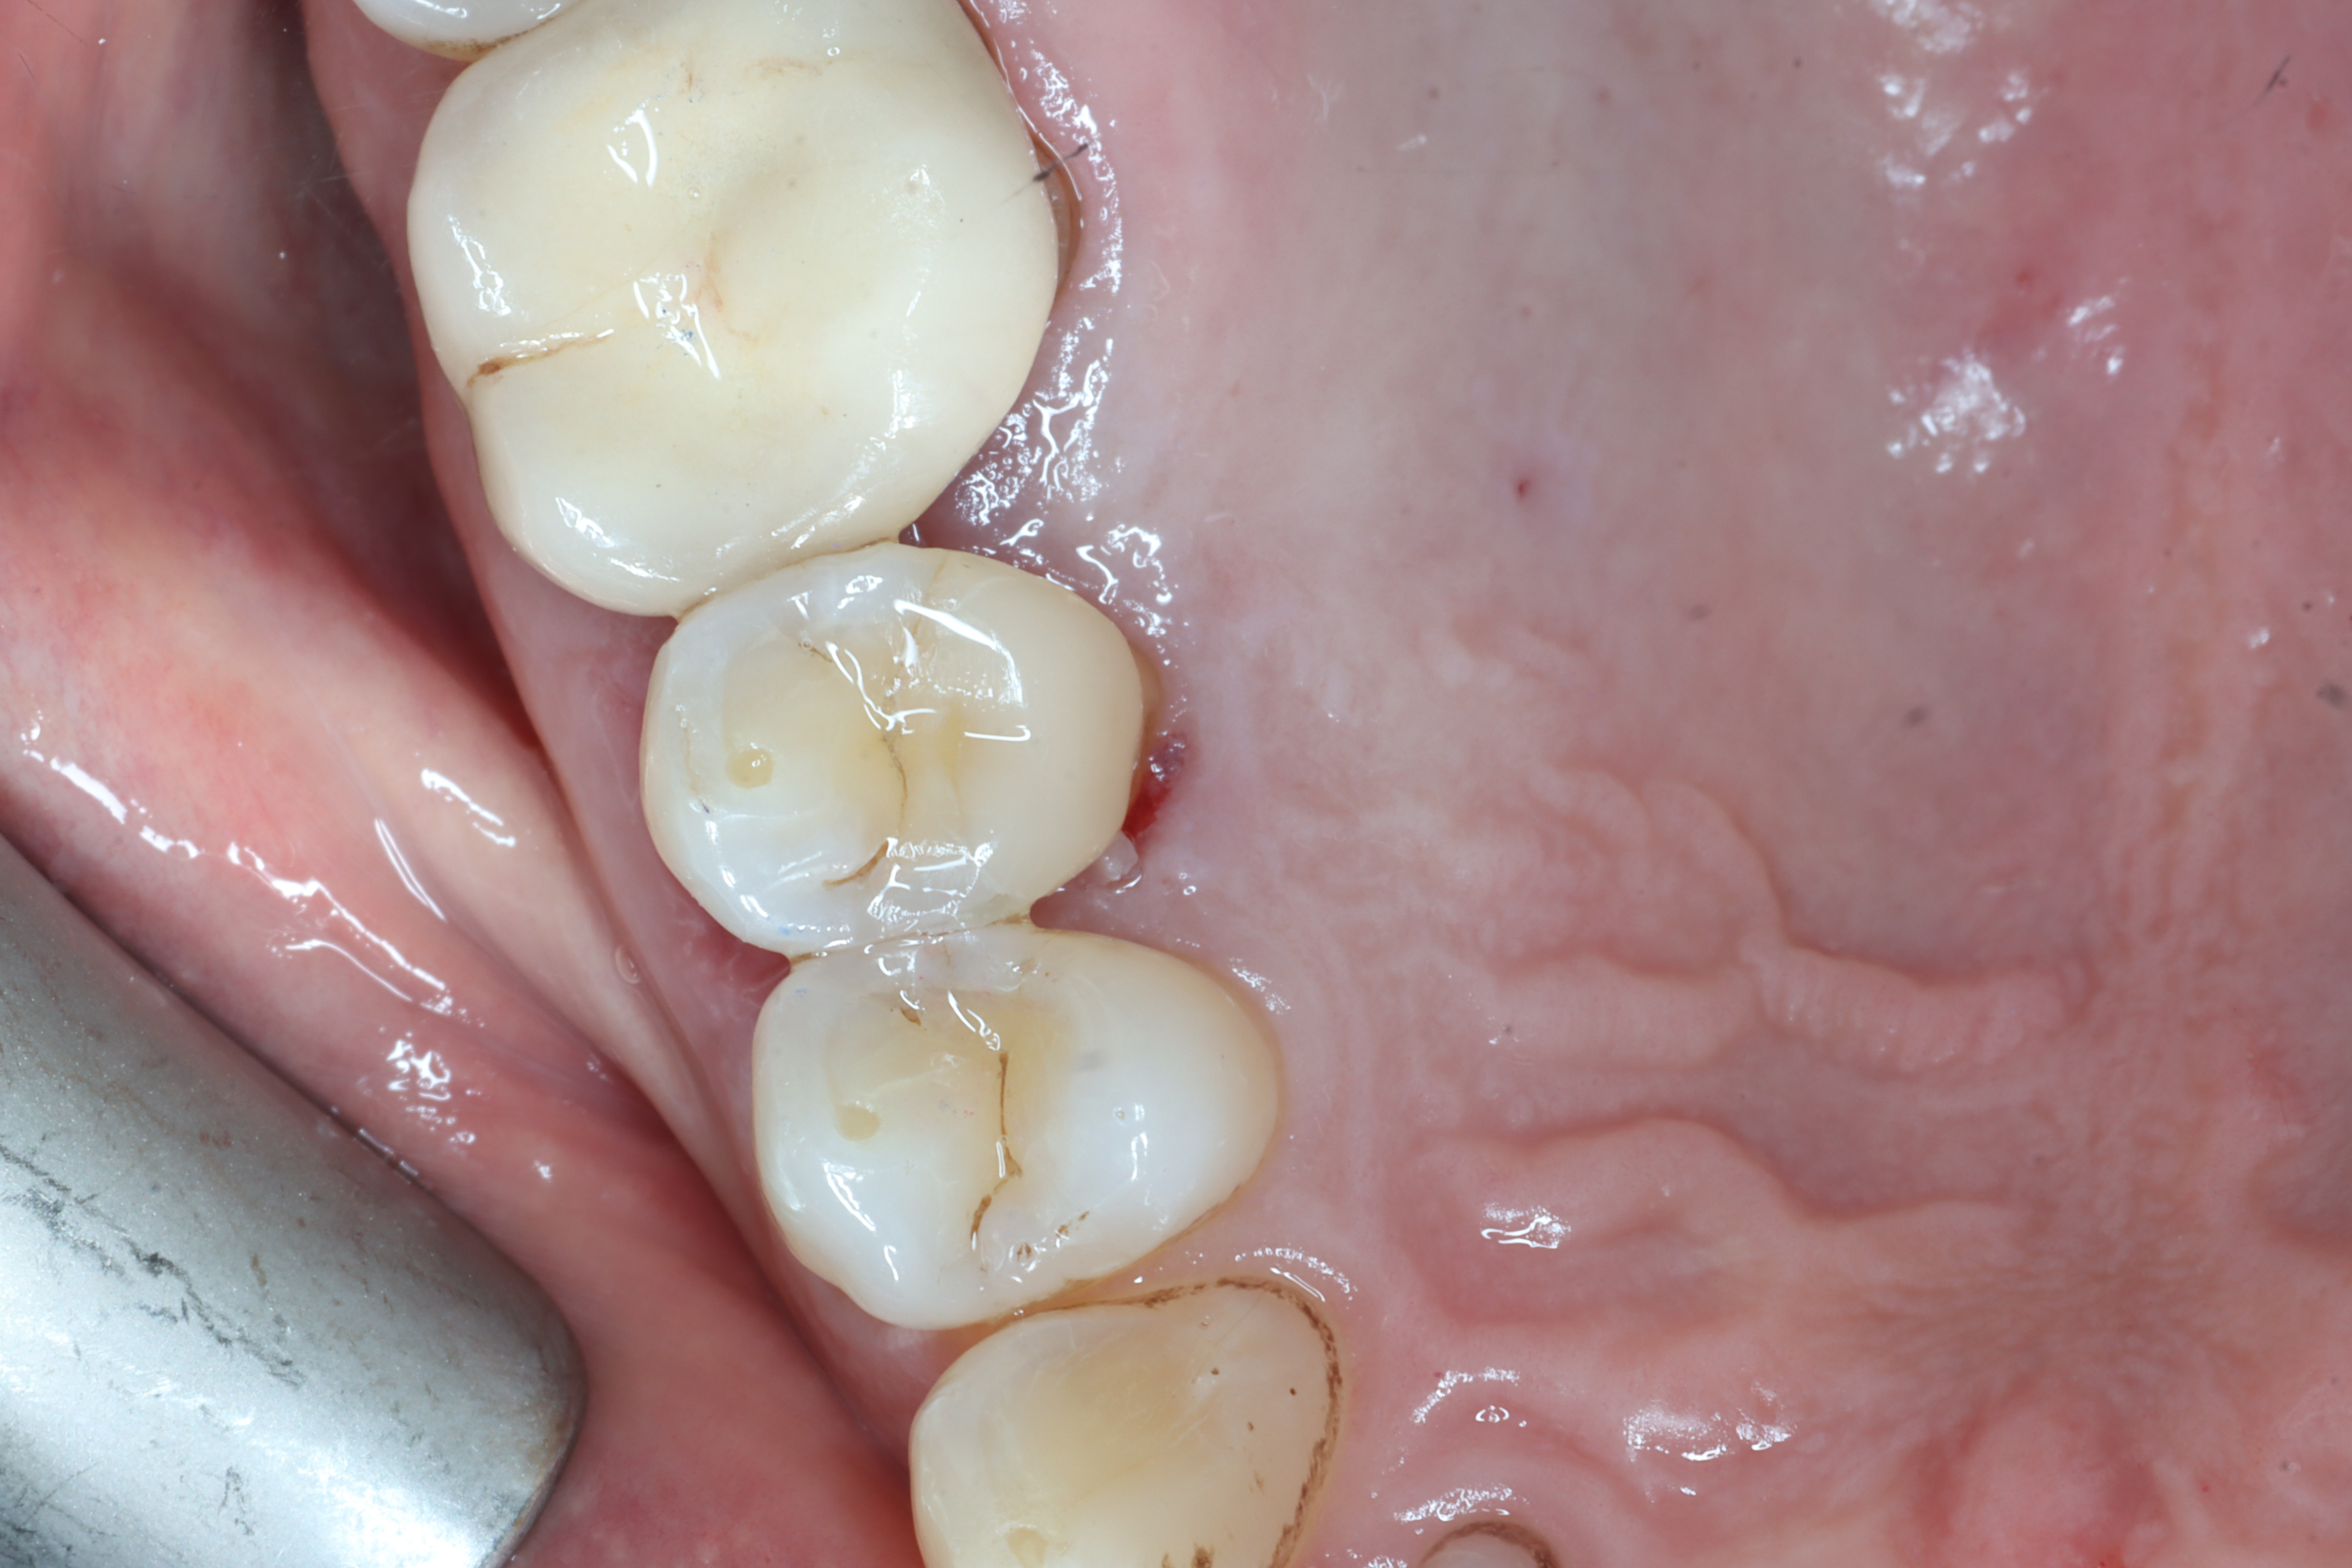

Case 6 – Periodontics

Crown lengthening Surgery on a premolar